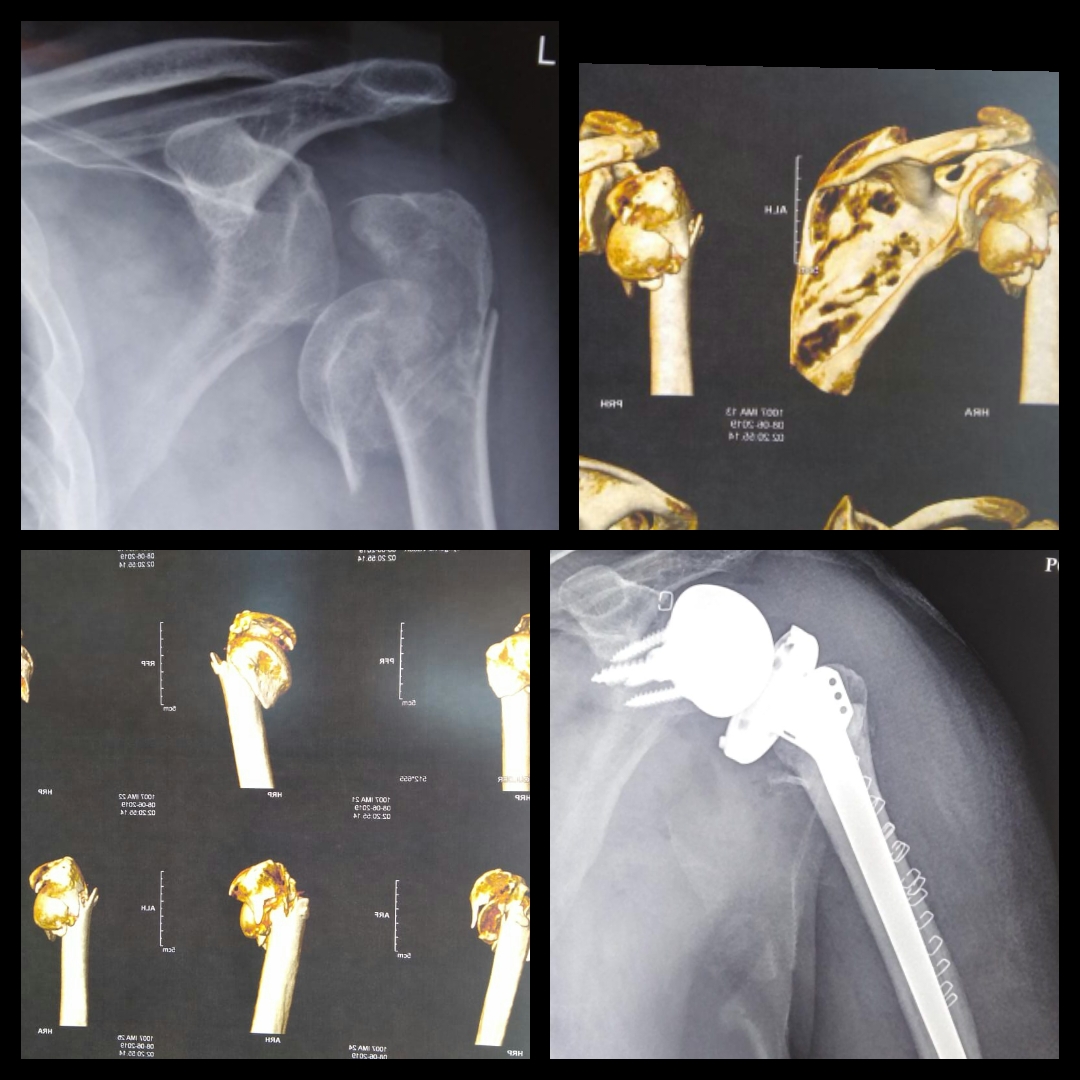

History: 83-yr-old man suffered from acute, three-part communited fracture of proximal humerus. Case: Fixation with plate screw would have been a futile exercise on 83-yr-old with weak bones and high quality fracture. A Hemi Replacement would fail too because of…

Read More